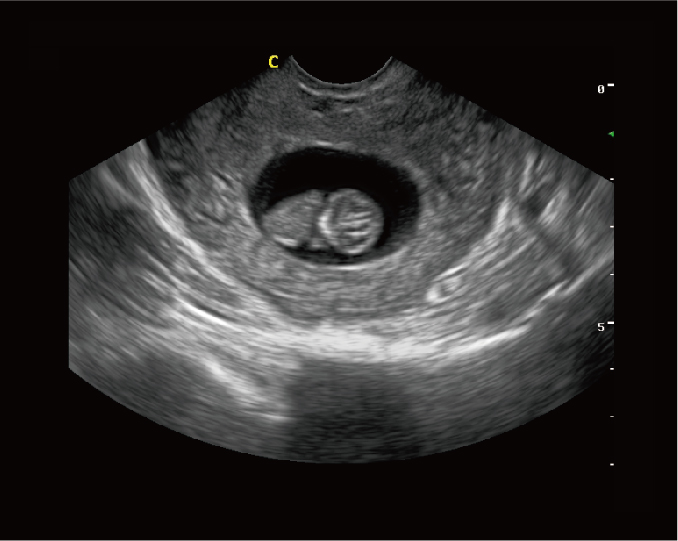

iVis 70

·洞悉瞬息变化,4D时代超声未来的发展需求,刚毅尺寸,丰富探头群,提供对心脏、产科、妇科、血管等临床需要 ·血管内膜自动测量(IMT) ·宽景成像 ·弹性成像

早孕,B模式